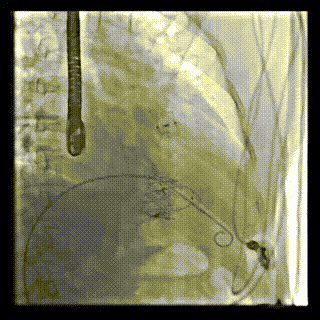

2021年12月24日,復(fù)旦大學(xué)附屬中山醫(yī)院葛均波院士團(tuán)隊(duì)成功應(yīng)用LuX-Valve Plus為一例極重度三尖瓣反流(TR)合并房顫、房缺的患者完成了經(jīng)血管三尖瓣置換術(shù),這是在前基礎(chǔ)上,本周完成的第三例經(jīng)血管三尖瓣置換手術(shù),葛均波院士、周達(dá)新教授等與心外科魏來教授、賴顥教授,心超室的潘翠珍教授、李偉教授及麻醉科的郭克芳教授共同完成了本周手術(shù),均獲得圓滿成功!患者術(shù)后超聲顯示無TR,臨床癥狀明顯改善。本周手術(shù)的成功也為L(zhǎng)uX-Valve Plus救治性臨床研究添上了濃墨重彩的一筆。

本周三例接受LuX-Valve Plus經(jīng)血管三尖瓣置換術(shù)的患者中,第一例患者為冠狀動(dòng)脈旁路移植術(shù)+Bentall+二尖瓣成形術(shù)后;第二例患者為永久起搏器植入術(shù)后,存在跨三尖瓣導(dǎo)線;第三例患者合并房顫、房缺及左心耳封堵術(shù)后。

三例患者入院后,葛均波院士團(tuán)隊(duì)周達(dá)新教授、潘文志教授、張?jiān)床┦俊㈥惿┦考靶某业呐舜湔浣淌凇⒗顐ソ淌趯?duì)患者的情況進(jìn)行詳細(xì)評(píng)估和討論,最終決定為三例患者選擇LuX-Valve Plus40mm、50mm和50mm型號(hào)的瓣膜進(jìn)行手術(shù)治療。手術(shù)后即刻拔除氣管插管,術(shù)后患者三尖瓣反流癥狀得到顯著改善,復(fù)查心超結(jié)果顯示人工三尖瓣瓣膜支架固定穩(wěn)定,瓣葉關(guān)閉形態(tài)未見異常,未見明顯反流。